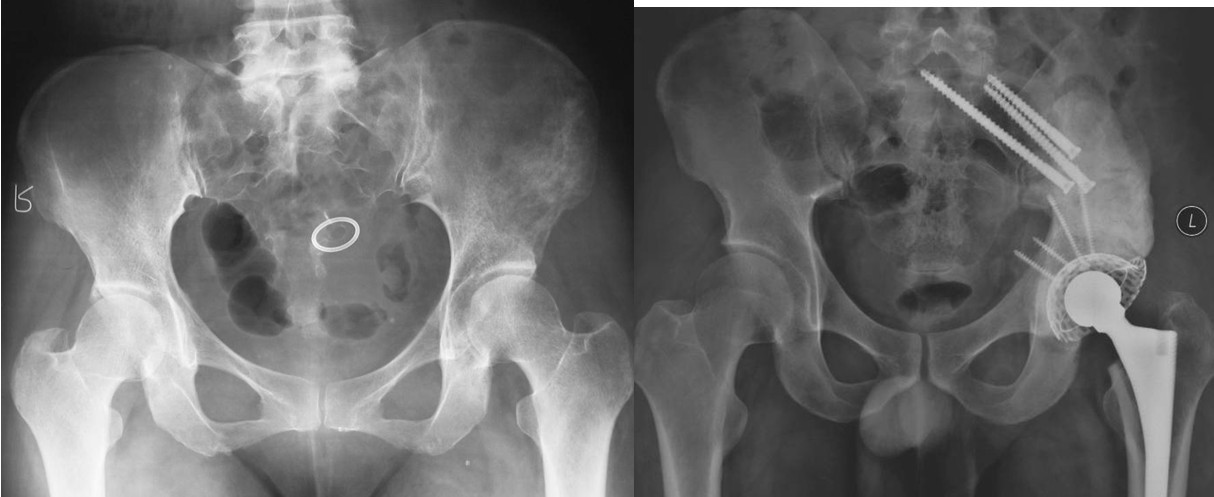

图5,男,69岁,肾癌髋臼转移, Harrington IV型